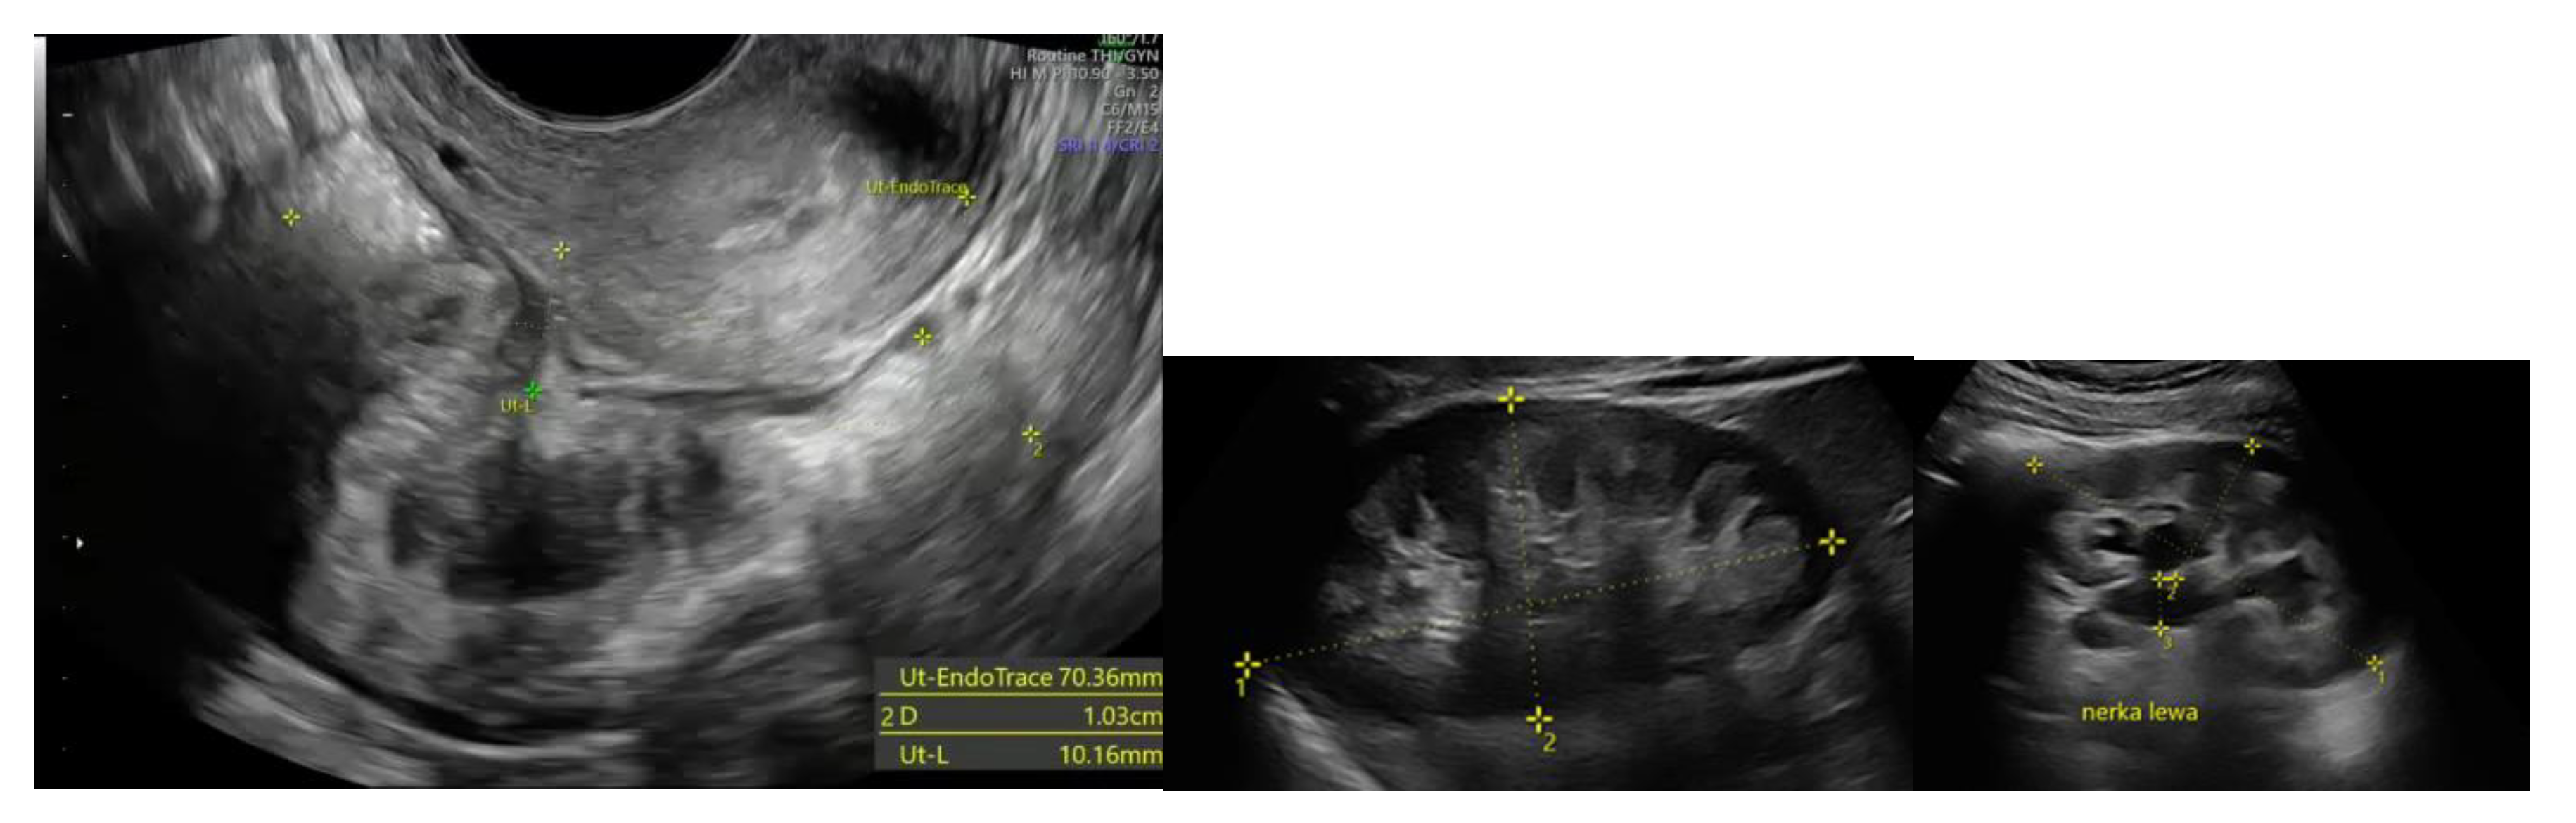

All patients underwent preoperative ultrasound examination by an expert surgeon-gynecologist – (E.M.-N.), with detailed pelvic compartments assessment via transvaginal sonography (TVS) and with kidney congestion assessment via transabdominal sonography (TAS), following an adapted protocol based on IDEA group guidelines. [7] Examinations were performed on Voluson E8 Expert with the use of vaginal probe RIC5-9-D (depth max 16 cm) and abdominal probe RAB2-5-D. Detailed report was recorded for each patient. Examples of ultrasound examination images are shown in Figure 1.

Figure 1. Preoperative ultrasound examination: the bowel DE nodule ( TVS exam), congestion in the left kidney (TAS exam).